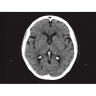

Компьютерный томограф GE Brivo CT385 представляет собой современное диагностическое оборудование, сочетающее высокую точность исследований с повышенным комфортом для пациентов. Этот аппарат открывает новые возможности для детальной визуализации анатомических структур.

Позволяет проводить комплексные исследования всех анатомических зон, включая нейровизуализацию, ангиографию, исследования органов грудной и брюшной полости. Особенно эффективен для раннего выявления онкологических заболеваний.